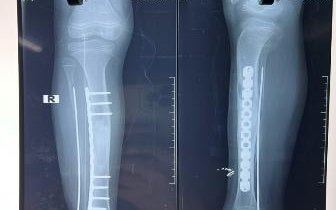

Căn bệnh hiếm "loạn sản xơ xương" khiến 2 chân bé 10 tuổi không bằng nhau

PLBĐ - Gia đình nghĩ con bị đau chân do chạy nhảy nhiều nhưng kết quả thăm khám cho thấy, cẳng chân trẻ bị biến dạng do loạn sản xơ xương hiếm gặp.